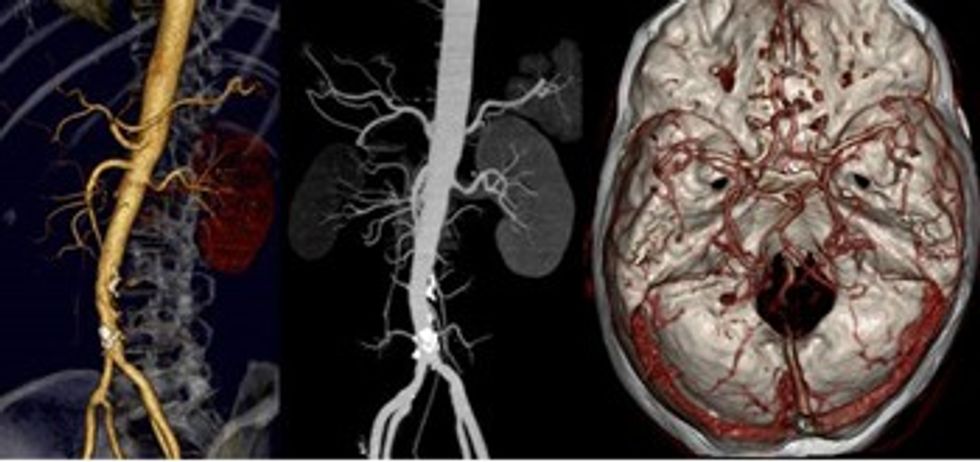

Enët e gjakut, arteriet dhe venat e çdo pjese të trupit mund të vlerësohen në tërë gjatësinë e tyre si dhe nga të katër anët.